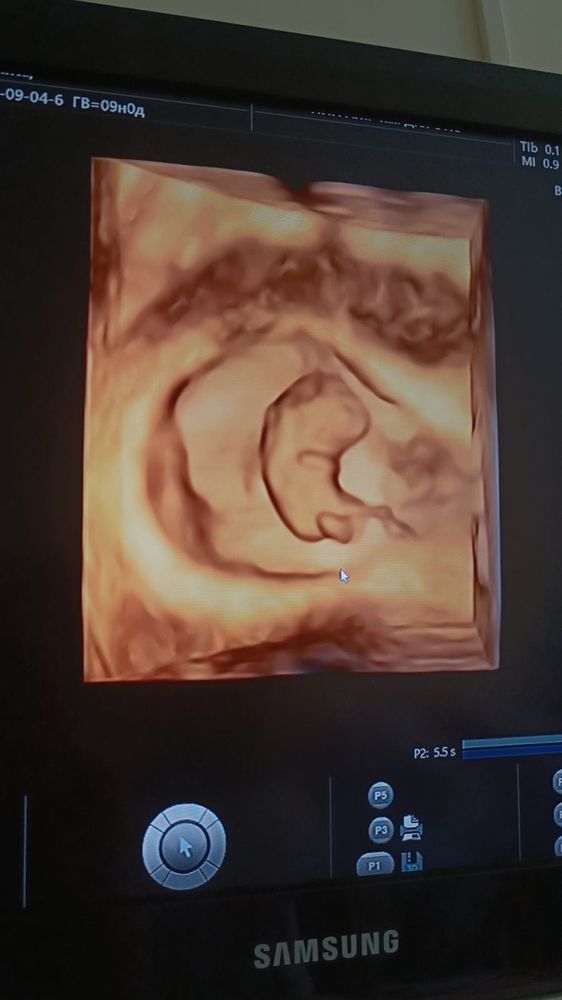

Результаты УЗИНам сегодня ровно 9 неделек, и в честь этого события наша замечательная сурмама Алиса отправилась вставать на учет по беременности.

Сегодня показали нам нашу "креветочку" во всей красе.

И наша малышка даже передала привет маме с папой: мило помахала ручкой в монитор 😍